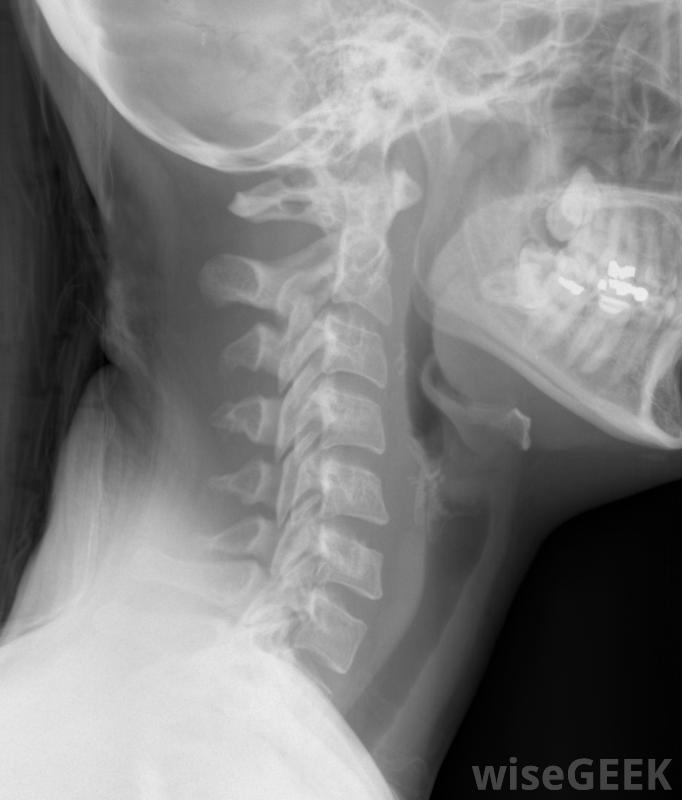

颈椎椎板切除术是对颈椎进行的几种可能的手术之一在开始颈椎椎板切除术时,外科医生首先要在脊椎上切开一个切口,然后用x光片确认每一个椎体的正确性,然后医生可以取出椎板,以及任何可能压迫神经的骨刺或其他外来物质。在某些情况下,外科医生会在椎板上切开并折叠起来,而不是完全切除。在去除所有必要的材料后,外科医生可以将切口缝合在一起在颈椎椎板切除术后恢复过程中,患者可能需要佩戴颈托。这将在该区域愈合时保持头部静止。具体所需的恢复时间因患者而异。外科医生会建议患者何时可以恢复工作和其他正常活动。有些患者可能会进行身体锻炼手术后的治疗。如果手术中出现任何并发症,患者可能需要额外的治疗。颈椎椎板切除术的一些可能的并发症包括感染、出血,病人在手术前应仔细考虑是否有脊髓损伤或神经损伤的独特情况。有时也要注意病人是否有脊髓损伤或神经损伤进行颈椎椎板切除术。